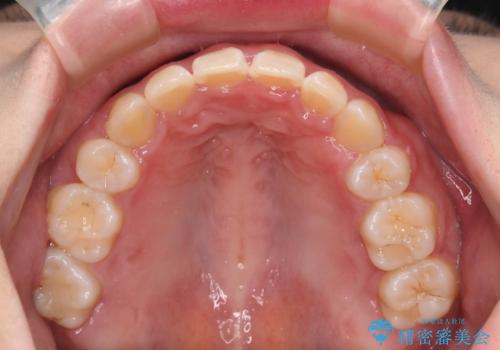

- 前歯のガタつきと口元の改善を主訴に来院されました。

なるべく目立たない装置が良いというご要望と、口元を引っ込めたいというご要望を両方達成するために今回はハーフリンガル装置を選択し治療計画の立案を行いました。

結果的に表の装置よりは期間が掛かりましたが、口元もしっかり下がり韓国美人な横顔になったと患者様にも喜んでいただけました。